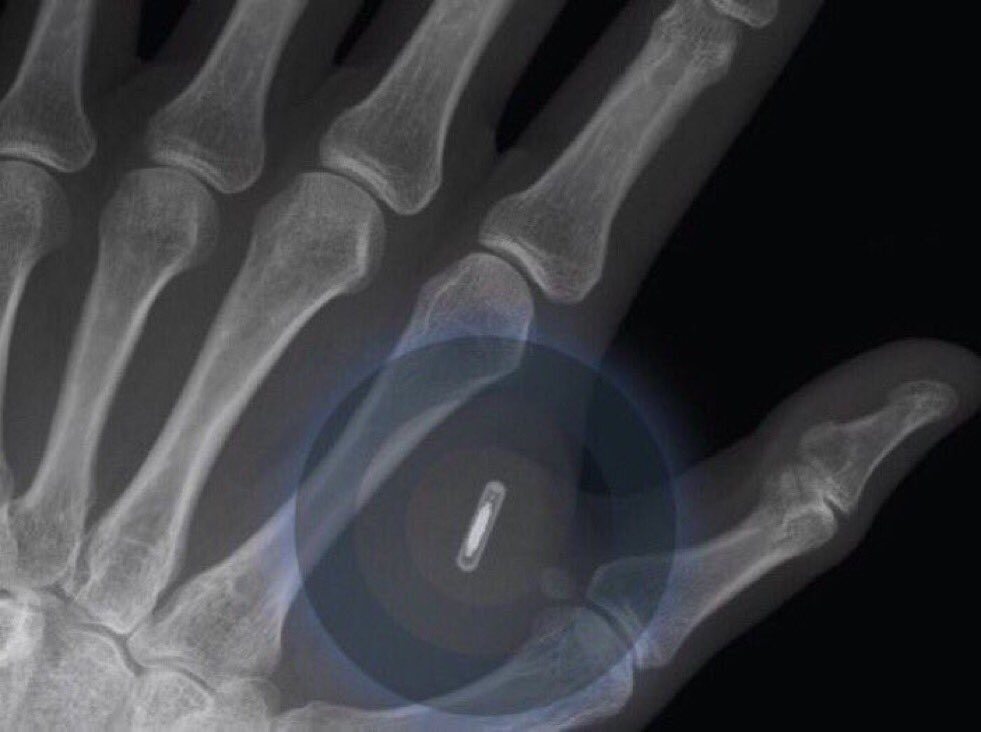

이렇다고 한다. 사진 보는데.. 살짝 소오름...

@ValaAfshar The first implantable mobile phone will become commercially available in 2025. — @wef #IoT

Co2_LRxWcAA5j4O.jpg